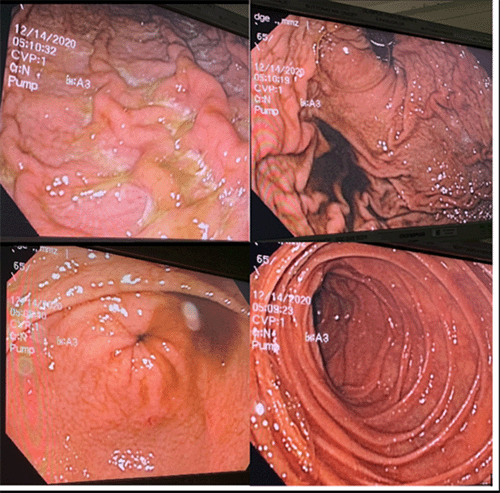

Figure 2. Intraoperative EGD. Published with Permission.

Composite of intraoperative endoscopic images. (Top left and top right) Views of the gastric body and fundus showing areas of purulent exudate and mucosal cobblestoning, consistent with severe gastritis. Despite these changes, the underlying gastric mucosa appears viable and perfused. (Bottom left) Endoscopic view of a patent pylorus. (Bottom right) Endoscopic view of the proximal duodenum, appearing normal and well-perfused. No evidence of frank ulceration, necrosis, or perforation was identified

The EGD revealed gastric mucosal cobblestoning, but no evidence of ulceration, necrosis, or ischemia (Figure 2). Laparoscopic examination showed no external signs of gastric necrosis or perforation; the omentum was noted to be covering the anterior gastric wall. The stomach wall itself appeared pink and well-perfused, with evidence of gastritis and some purulent exudate on the gastric mucosa. Critically, gas was observed actively escaping through a defect in the capsule of the left lobe of the liver, correlating with the location of the hepatic portal venous gas collections seen on the preoperative CT scan. The small and large bowel were thoroughly inspected and showed no signs of ischemia or perforation. No succus or fecal contamination was noted within the peritoneal cavity to suggest a hollow viscus perforation. The only identifiable source of the pneumoperitoneum was the escape of gas from the ruptured left liver lobe capsule. Laparoscopic access was obtained at the umbilicus using an open Hasson technique. A Jackson-Pratt (JP) drain was placed in the left upper quadrant, and the laparoscopic ports were removed.